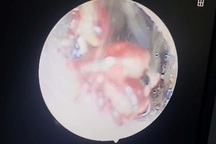

Ấu trùng trong tai bé gái, gây thủng nhĩ (Ảnh: BVCC).

Bác sĩ tiến hành nội soi, phát hiện một dị vật trong tai phải của bé T. còn đang cử động gây thủng nhĩ. Ngay sau đó, bác sĩ tiền mê để bé không sợ hãi và quấy khóc và lấy ấu trùng ra khỏi tai bé.

Ấu trùng lấy ra từ tai của bé gái 16 tháng tuổi (Ảnh: BVCC).

Theo bác sĩ Trứ, đây là một trường hợp khá hy hữu khi ấu trùng chui vào tai em bé gây thủng nhĩ.